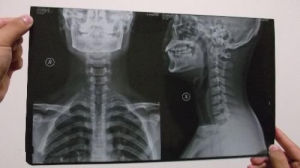

正常頸椎生理曲度從側方看人體在端坐或站立時的頸部似乎是直的,其實包繞於內的頸椎並不是直的,而是在其中段有一向前凸出的弧度。在醫學上把這一向前的弧形凸起稱為頸椎的生理曲度。通過X線片上的頸椎顯像:沿此曲度走行,在各個頸椎椎體後緣都有形成的連續 、光滑的弧形曲線,醫學上稱之為頸椎曲度。當長時間不正確的坐姿、或是長時間的勞累、頸椎缺少活動、脊柱損傷、脊柱鈣化等就會導致頸椎生理曲度變直。

頸椎生理曲度的存在,能增加頸椎的彈性,減輕和緩衝重力的震盪,防止對脊髓和大腦的損傷。由於長期坐姿、睡姿不良和椎間盤髓核脫水退變時,頸椎的前凸可逐漸消失,甚至可變直或呈反張彎曲,即向後凸,成為頸椎病X線上較為重要的診斷依據之一。

具有頭、肩、頸、臂的疼痛及相應的壓痛點,X線片上沒有椎間隙狹窄等明顯的退行性改變,但可以有頸椎生理曲線的改變,椎體間不穩定及輕度骨質增生等變化。此型在臨床上極為常見,是最早期的頸椎病。由於症狀較輕,往往重視不夠,以致反覆發作使病情加重,不少反覆落枕的病人即屬於此種改變。從大量的臨床觀察證實,此型實際上是頸椎病的最初階段,也是治療最為有利的時機。